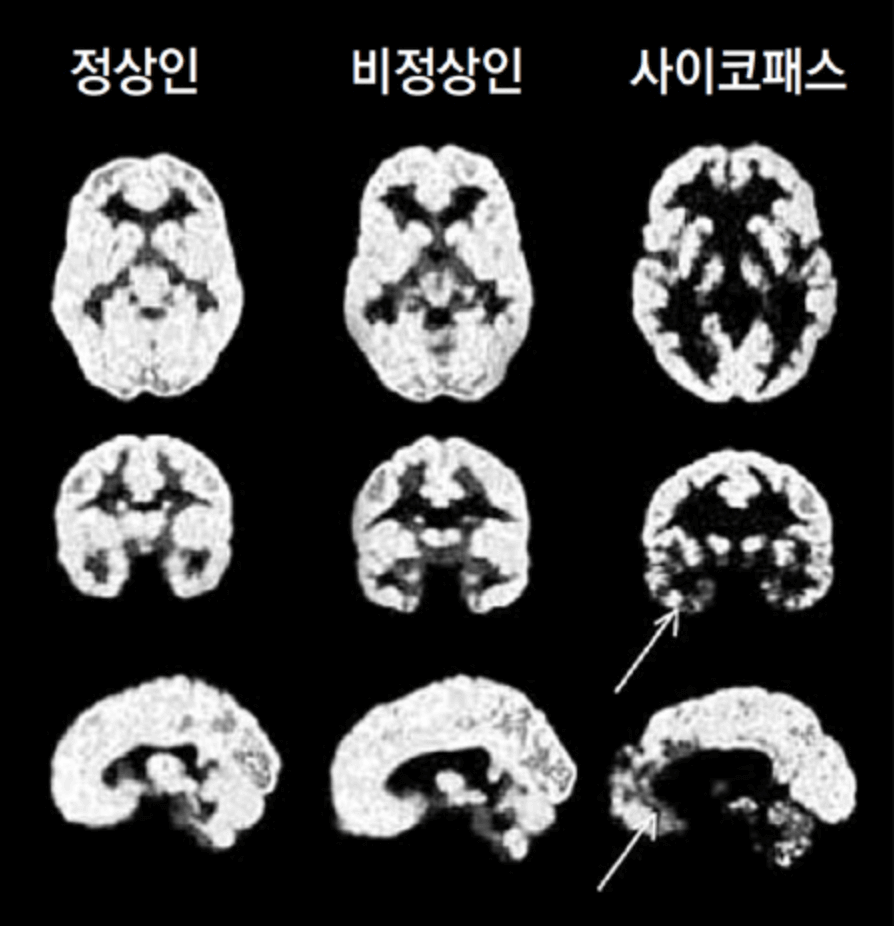

먼저 뇌 사진을 한번 보여드릴게요.

다른 점이 확연히 느껴지시죠? 사이코패스의 뇌는 CT사진을 보면 정상인에 비해 흰색 부분이 굉장히 적다는 것을 볼 수 있어요.